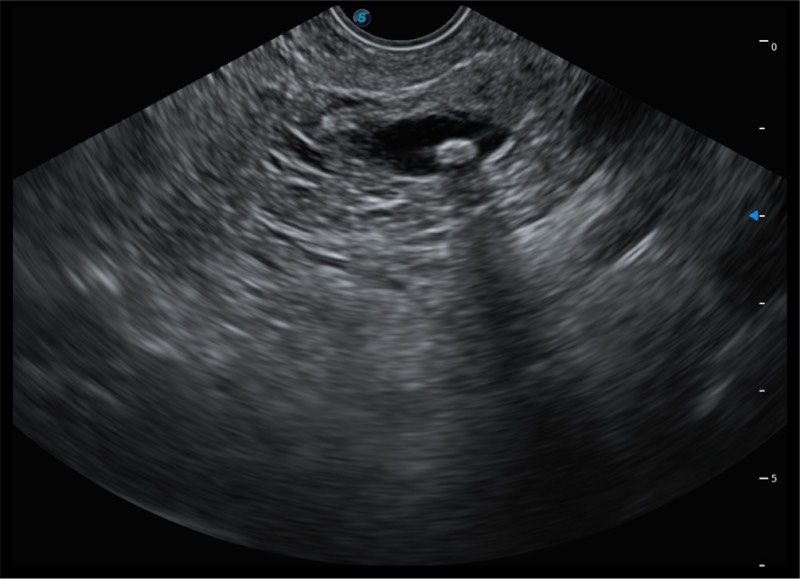

• 搭载百万级CMOS成像技术

• 及自主研发凸阵换能器,

• 可呈现优质的内镜和超声画面

基于二十年的超声技术积累,db真人体育官网提供了最新一代的独立超声主机,在提供高质量图像的同时满足多学科使用。具备常见多普勒技术并提供弹性成像、声学造影等高端影像技术。新一代传感器具有更强的抗干扰能力并减少图像伪影。

• 150°超声扫描角度

• 4-12MHZ宽频输出